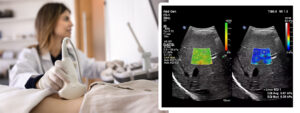

El avanzado departamento de ultrasonido de Zwanger-Pesiri Radiology ahora ofrece Elastografía por Ultrasonido del Hígado, una forma innovadora y no invasiva de evaluar la salud del hígado. Este examen ayuda a los médicos a evaluar la rigidez del hígado, un indicador importante de fibrosis o cicatrización, sin necesidad de procedimientos más invasivos. Al combinar la imagenología por ultrasonido tradicional con tecnología avanzada, los pacientes se benefician de una experiencia diagnóstica más segura, rápida y cómoda.

La elastografía por ultrasonido funciona utilizando ondas sonoras para medir cuán rígido o elástico es el tejido hepático. Durante el examen, el dispositivo de ultrasonido envía pulsos suaves a través del hígado. Estos pulsos crean ondas de cizallamiento que viajan por el tejido, y se mide la velocidad a la que se desplazan. Un tejido hepático más rígido permite que las ondas viajen más rápido, lo que puede indicar fibrosis u otras anormalidades. Los resultados se traducen luego en datos cuantitativos que los médicos pueden usar para evaluar la salud del hígado y guiar decisiones de tratamiento.